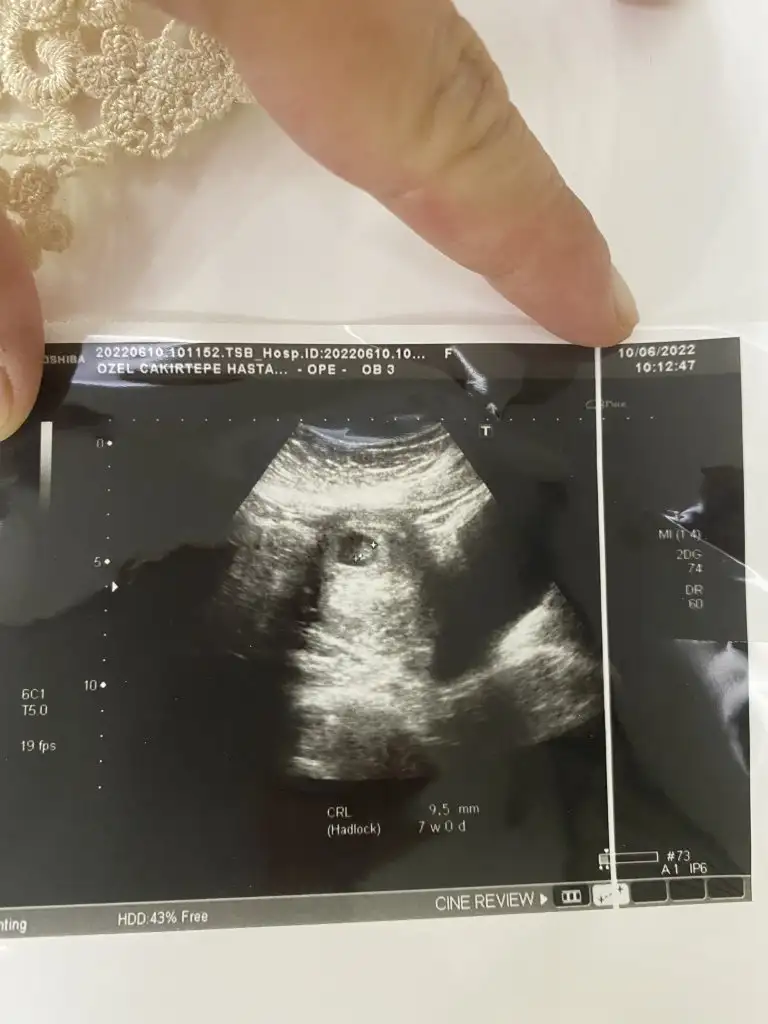

prenses gibiMerhaba benimkinide bakabilirmisiniz 3.hamileleik 7.0 hafta karından

sanki prenses gibiMerhabaPasha22 bana da yorum yapabilir misin biri 6+1 diğeri 8+1 karından